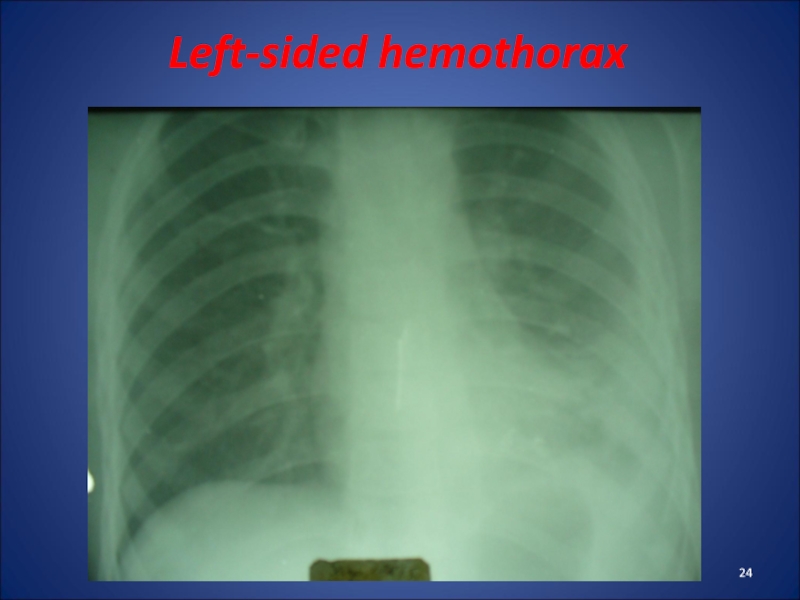

Слайд 24Left-sided hemothorax

Left-sided hemothorax

Слайд 23Clinic of Hemothorax

rapid weak pulse, tachypnea, decreased AP, pale skin.

In patients there are pain in the affected side of

the chest, cough.

Percussion - dull sound, auscultation - missing or weakened breathing. After 3-6 days the body temperature rises.

Radiologically – eclipse, shift shadowof heart in a healthy side.

Treatment: pleural puncture (not earlier than 3-4 days). Earlier puncture can help to restore bleeding. Also, spend haemostatic and infusion therapy.

Clinic of Hemothoraxrapid weak pulse, tachypnea, decreased AP, pale skin. In patients there are pain in the